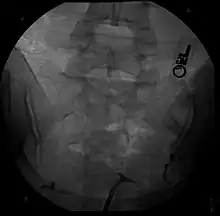

Hysterosalpingography of a T-shaped uterus

The uterine cavity has a "T-shape" as a result of fetal exposure to diethylstilbestrol.